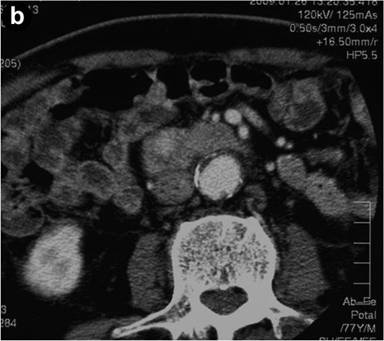

A 72-year-old man was admitted to our hospital with jaundice. He had a 15-year history of diabetes mellitus. There were no palpable masses or lymph nodes at physical examination. Full blood count and renal values were normal, but liver biochemistry showed total bilirubin of 11.7 mg/dL (reference range: 0.2-1.0 mg/dL), direct bilirubin of 8.8 mg/dL (reference range: 0.1-0.4 mg/dL), AST of 88 IU/L (reference range: 0-40 IU/L), ALT of 184 IU/L (reference range: 0-40 IU/L), alkaline phosphatase of 3,414 IU/L (reference range: 115-360 IU/L) and GGT of 1,356 IU/L (reference range: 10-60 IU/L). The serum level of CA 19-9 was elevated to 69 U/mL (reference range: 0-37 U/mL), that of DUPAN-2 was 1,320 U/mL (reference range: 0-150 U/mL) and that of SPAN-1 was 63 U/mL (reference range: 0-150 U/mL). Computed tomography showed dilatation of both the biliary tract and the main pancreatic ducts as well as an enhanced mass lesion measuring 1.5 cm in the pancreatic head (Figure 1). These findings suggested the existence of a tumor involving the ampulla of Vater. Endoscopic examination showed a reddish swollen papilla of Vater (Figure 2). Pathological findings on biopsy from the papilla suggested tubular adenocarcinoma and signet-ring cell carcinoma. Endoscopic examination of the stomach and the colon did not disclose any other foci of signet-ring cell carcinoma. Having diagnosed carcinoma of the ampulla of Vater, a pancreaticoduodenectomy was performed.

Figure 2. Endoscopic findings of the papilla of Vater. Endoscopic examination showed a reddish swollen papilla. |